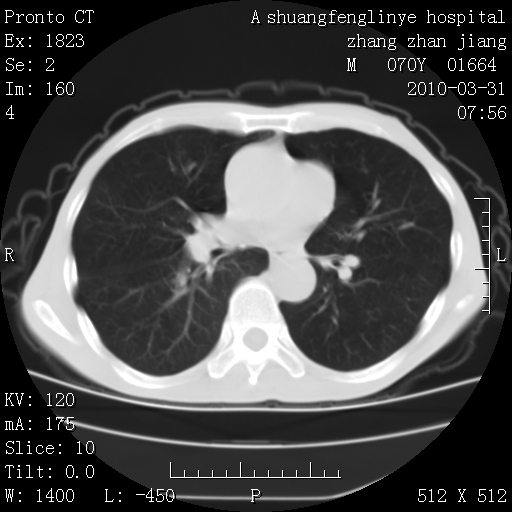

支持,不过左肺中叶那个像陈旧病变的结节要不要单报一下,在图上没看到钙化单报一下放心啊

双上肺继发型tb并左上空洞形成,主动脉冠脉钙化。

1)两肺上叶继发性肺结核并左肺上叶空洞形成。2)冠状动脉及主动脉钙化。